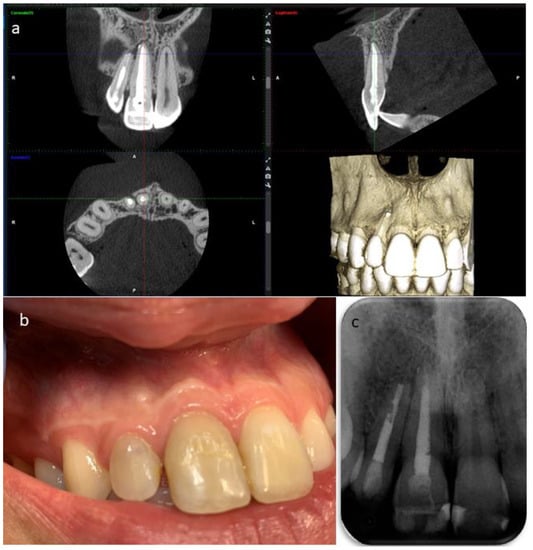

2. Case Report